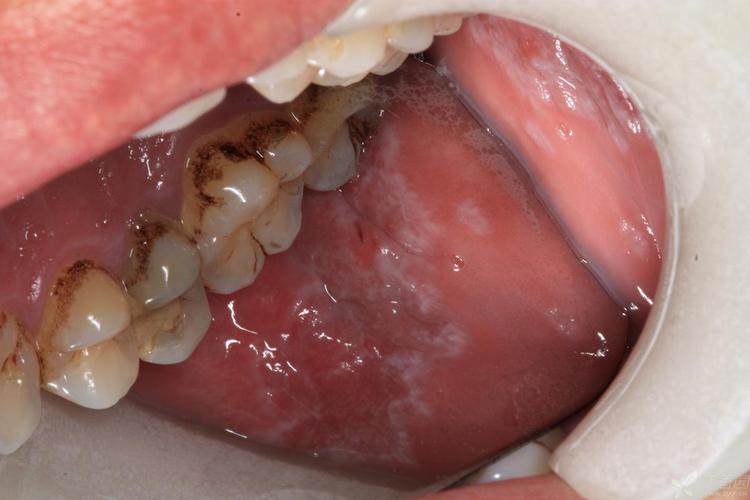

口腔黏膜的“网纹”与“花纹”(最典型)

这是扁平苔藓最具标志性的症状,早期时,这些白色条纹可能非常轻微,颜色略浅,呈灰白色或珠光色,与周围黏膜的界限清晰。

- 发生部位: 最常见于颊黏膜(内腮帮子),其次是舌缘、牙龈、唇部、硬腭等部位。

- 自我观察: 对着镜子,拉开腮帮子,观察内侧黏膜,如果看到一些平铺的、不高于黏膜表面的白色细线或网状结构,就要警惕了。

- 图示说明:

- 【图片1:颊黏膜典型网纹状OLP】

(图片描述:此图清晰展示了患者右侧颊黏膜上典型的白色网纹状损害,Wickham纹清晰可见,呈树枝样交错,周围黏膜正常。)

(图片来源网络,侵删) - 【图片2:舌缘OLP表现为白色条纹】

(图片描述:图片显示患者舌缘两侧可见多条平行的白色细条纹,排列整齐,是舌部扁平苔藓的常见表现。)